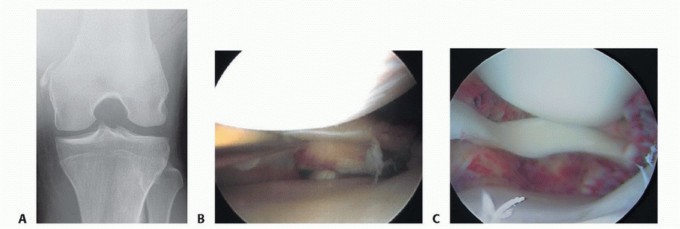

DEFINITION A medial collateral ligament (MCL) injury usually is the result of a valgus stress on the knee. Fo…

DEFINITION Synovial tissue is found lining the joint capsules and tendon sheaths of the body. Synovitis is ch…

DEFINITION Loss of motion is a generic term that can refer to a loss of flexion, extension, or both. It does …